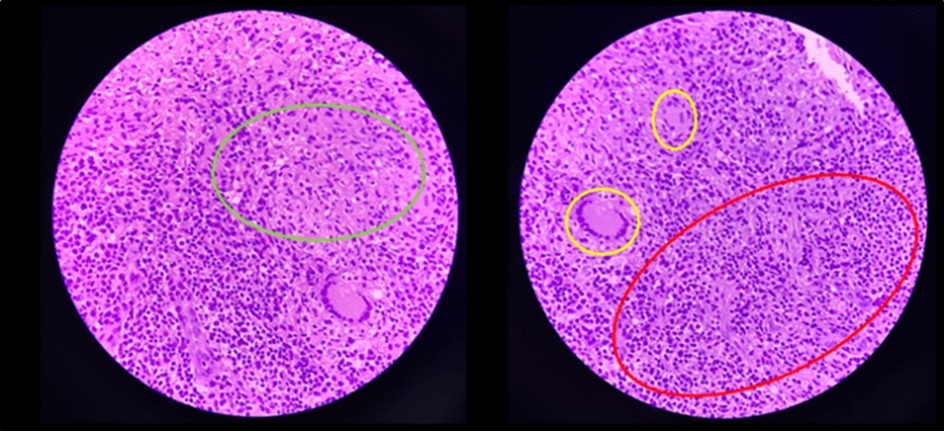

Biopsy showed chronic granulomatous inflammation with caseation necrosis and Langhan’s type giant cells consistent with tuberculous etiology (Figure 6, and Figure 7). TB PCR detected Mycobacterium tuberculosis, Rifampicin (MTB, RIF) resistance indeterminate. Category I Anti-TB treatment for six months was started and the service planned to repeat both colonoscopy and CT-scan after the initial round of anti-TB treatment. Currently, the patient is able to work with no abdominal pain and was able to tolerate her anti-TB drug regimen

Figure 7.Pathologic slide in the high power field. Inside the green circle is the epitheloid histiocytes. The yellow circles are the Langhan’s type multinucleated gian cells. And inside the red circle is the lymphocytic infiltrates. Which is suggestive of tuberculous etiology.